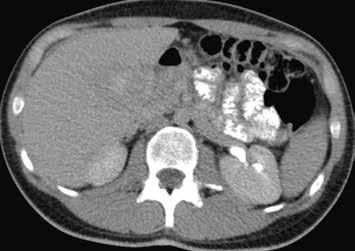

Nativně je v játrech ložisko, které je na CT hypodenzní (4), na MR izointenzní (5).

Na CEUS je v arteriální fázi patrný v levé polovině obrázku typický centrifugální charakter sycení ložiska, které je vidět v pravé polovině obrázku v B -módu (jako hypoechogenní) (6–8). Na CT (9) i MR (10) se ložisko (z obr. 4, 5) sytí homogenně, vyjma centrální vazivové jizvy, která zůstává hypodenzní.

V portovenózní fázi je ložisko izodenzní na CT (11), respektive izointenzní na MR (12).

V pozdní fázi je charakter ložiska stejný a nedochází k jeho vymývání ani na CT (13), ani na MR (14).

V centrální části ložiska je patrná vazivová jizva, která zůstává v arteriální fázi hypodenzní (9) a sytí se v pozdní fázi, kde je oproti zbytku ložiska hyperdenzní (13). Na MR je v T1-váženém obraze vazivová jizva hypointenzní (15), v T2-váženém obraze hyperintenzní (16).